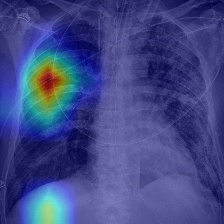

Recent epidemiological data report that worldwide more than 53 million people have been infected by SARS-CoV-2, resulting in 1.3 million deaths. The disease has been spreading very rapidly and few months after the identification of the first infected, shortage of hospital resources quickly became a problem. In this work we investigate whether chest X-ray (CXR) can be used as a possible tool for the early identification of patients at risk of severe outcome, like intensive care or death. CXR is a radiological technique that compared to computed tomography (CT) it is simpler, faster, more widespread and it induces lower radiation dose. We present a dataset including data collected from 820 patients by six Italian hospitals in spring 2020 during the first COVID-19 emergency. The dataset includes CXR images, several clinical attributes and clinical outcomes. We investigate the potential of artificial intelligence to predict the prognosis of such patients, distinguishing between severe and mild cases, thus offering a baseline reference for other researchers and practitioners. To this goal, we present three approaches that use features extracted from CXR images, either handcrafted or automatically by convolutional neuronal networks, which are then integrated with the clinical data. Exhaustive evaluation shows promising performance both in 10-fold and leave-one-centre-out cross-validation, implying that clinical data and images have the potential to provide useful information for the management of patients and hospital resources.